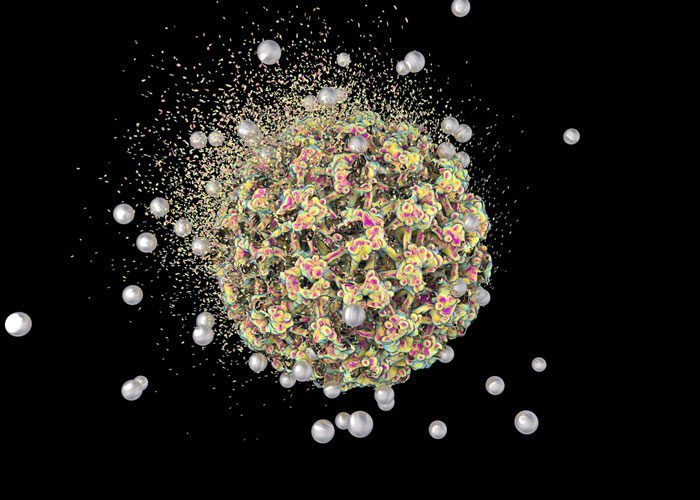

Scientists have developed ‘intelligent’ nanoparticles which heat up to a temperature high enough to kill cancerous cells – but which then self-regulate and lose heat before they get hot enough to harm healthy tissue.

The self-stopping nanoparticles could soon be used as part of hyperthermic-thermotherapy to treat patients with cancer.

Scientists from the University of Surrey’s Advanced Technology Institute have worked with colleagues from the Dalian University of Technology in China to create nanoparticles which, when implanted and used in a thermotherapy session, can induce temperatures of up to 45°C.

The Zn-Co-Cr ferrite nanoparticles produced for this study are self-regulating, meaning that they self-stop heating when they reach temperatures over 45°C. Importantly, the nanoparticles are also low in toxicity and are unlikely to cause permanent damage to the body.